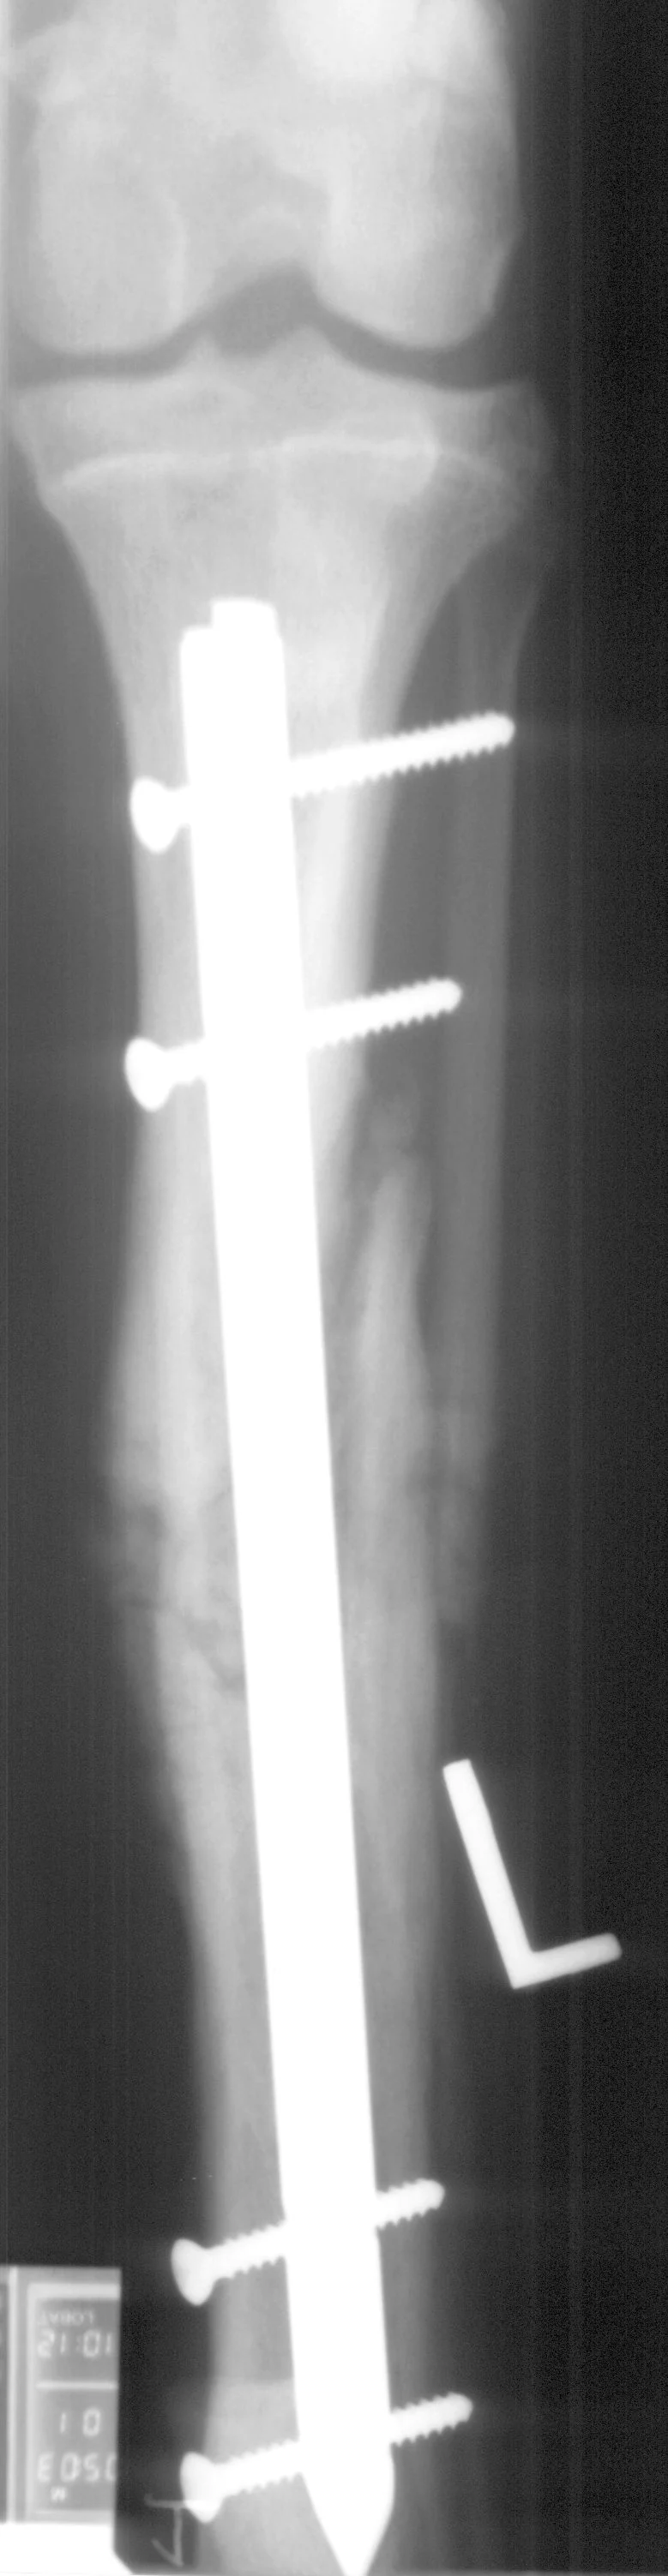

Fractures managed using interlocking nails and biologic technique develop extensive bridging callus and early return to function. A minimally invasive surgical approach (note the surgical skin staples) was made to this fracture to minimize disruption of the blood supply to the bone fragment. The fracture fragments quickly become incorporated in the callus if soft tissue attachments can be maintained.

Healing of the comminuted tibial fracture shown in Figures 2A and 2B after stabilization using an interlocking nail system. This fracture reached bony union in 8 weeks.